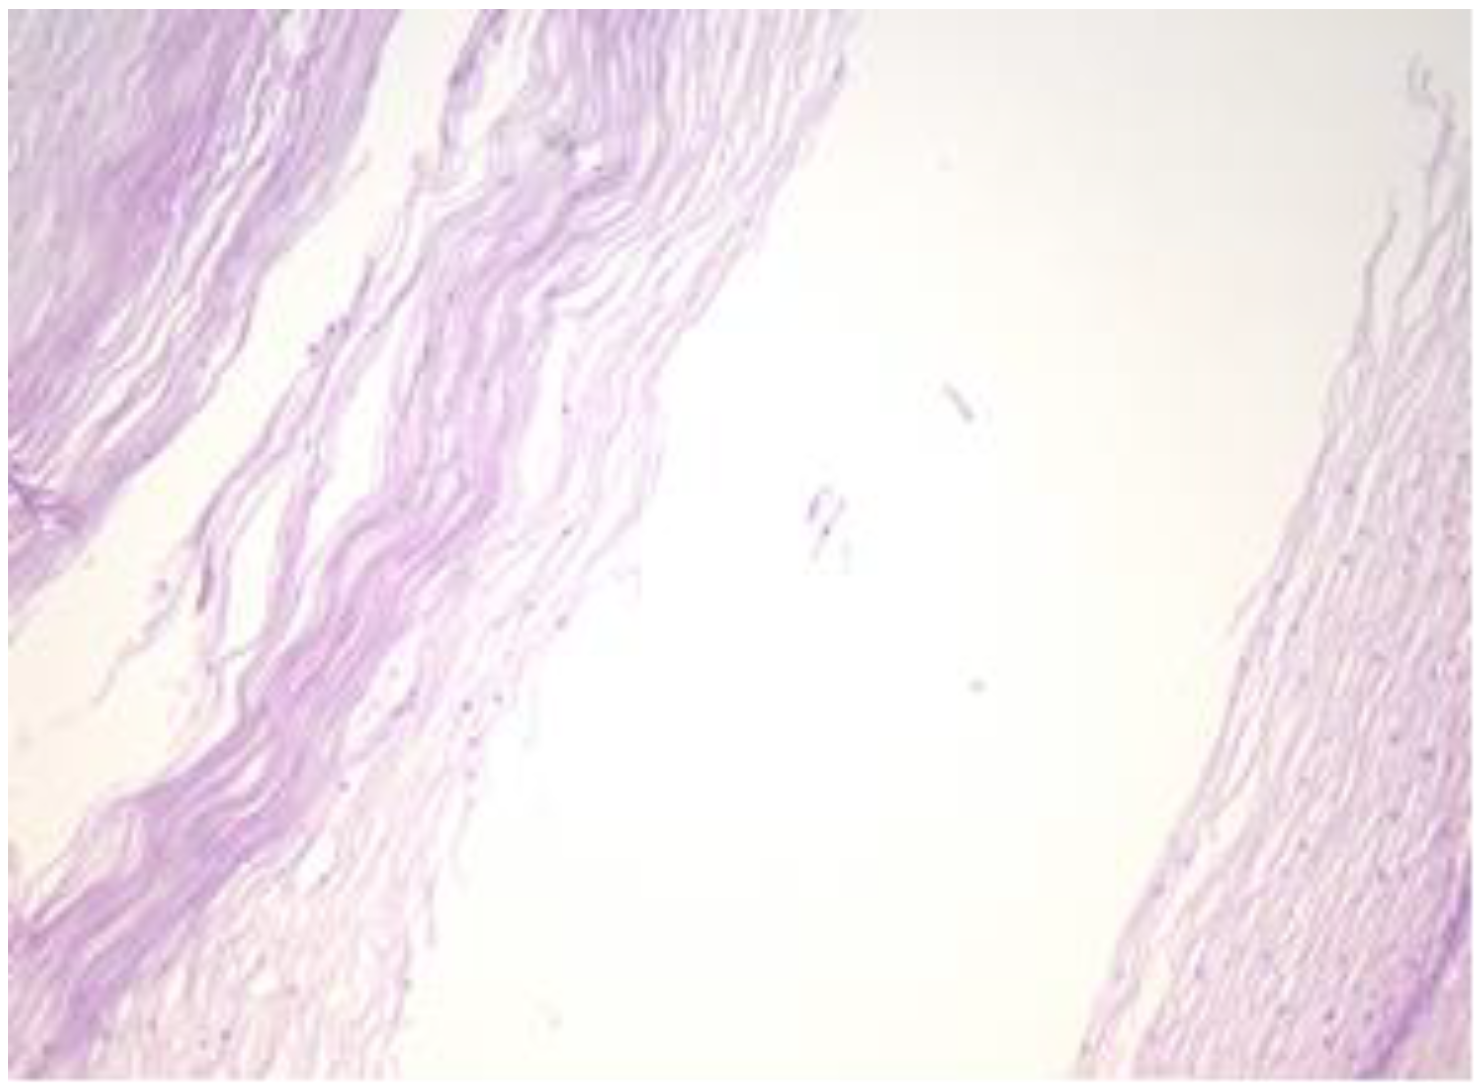

Other areas of the cyst are lined by stratified, flattened epithelium with focally outer fine, but distinct, granulated eosinophilic cytoplasm cells (Figure 5). The cyst’s epithelium, content and overlying exocervical epithelium are marked positive (Figure 6). The epithelium of the cyst is also marked as intensely positive (Figure 7). The myometrium presents islands of endometrial stromal and glandular structures within its thickness. In the endometrium, we are able to assess the ratio between the glandular structures and stroma and we notice that it is strongly modified in the gland’s favour. Para tubal, we see a cystic structure with amorphic, slightly eosinophilic content. This cystic formation is lined at the most intimate level by a single layer of cuboidal, cylindrical cells, sometimes presenting a flattened structure.

Figure 5.

Other areas of the cyst are lined by a stratified, flattened epithelium with focally outer fine, but distinct, granulated eosinophilic cytoplasm cells (HE staining, 40×).